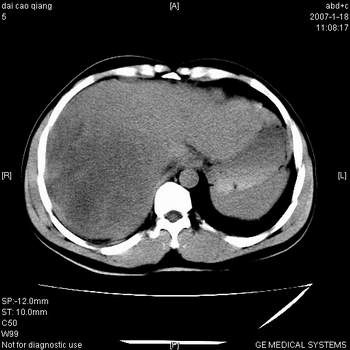

符合巨块型肝癌表现:

1、平扫低密度,增强后表现为快进快出。

2、动脉期可见迂曲的动脉供血血管

3、并可见门静脉右支癌栓形成

4、可见假包膜

5、腹主动脉旁结节影,考虑肿大淋巴结。

肝右叶巨大不均匀低密度肿块,前缘有假包膜,增强明显的呈快进快出表现,门脉右支有癌栓,病人虽然年轻但还是首先考虑肝右叶巨块形肝癌,病人血象高只能说有合并感染。不支持肝脓肿。